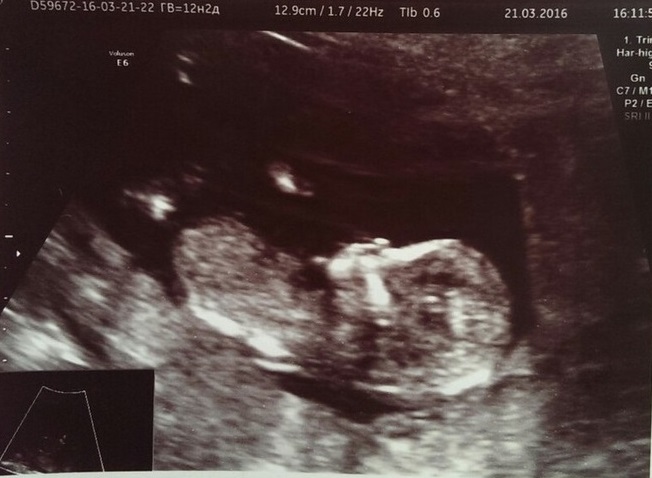

Первый скрининг.

КТР- 63,7 мм

ТВП- 1,5 мм

БПР- 22,0 мм

ЧСС- 157 уд.

Локализация- задняя стенка.

Срок 12 недель 5 дней.